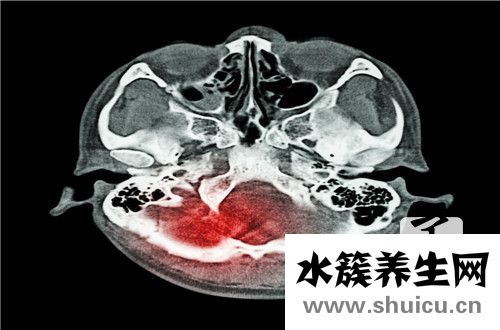

慢性硬膜下血肿是一个常见的脑部问题。这种问题的发生对病人来说是比较严重的。如果治疗不及时或治疗方法不正确,很可能导致患者出现痴呆、偏瘫等症状,甚至直接导致患者死亡。因此,当出现慢性硬膜下血肿时,必须及时进行治疗!

慢性硬膜下血肿是指